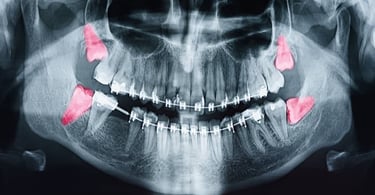

ABOUT THE DENTAL IMPLANT PROCEDURE

Dental implants are metal anchors, which act as tooth root substitutes. They are surgically placed into the jaw bone. Small posts are then attached to the implant, which protrude through the gums. These posts provide stable anchors for artificial replacement teeth.

For most patients, the placement of dental implants involves two surgical procedures. First, dental implants are placed within your jaw bone. For the first three to six months following surgery, the implants are beneath the surface of the gums, gradually bonding with the jaw bone. You should be able to wear temporary dentures and eat a soft diet during this time. At the same time, your restorative dentist designs the final bridgework or denture, which will ultimately improve both function and aesthetics.

After the dental implant has bonded to the jaw bone, the second phase begins. The surgeon will uncover the implants and attach a small healing collar. Dr. Prasad and Dr. Siddhi can then start making your new teeth. An impression must be taken. Then posts or attachments can be connected to the implants. The replacement teeth are then made over the posts or attachments. The entire procedure usually takes 3 to 6 months. Most patients do not experience any disruption in their daily life.